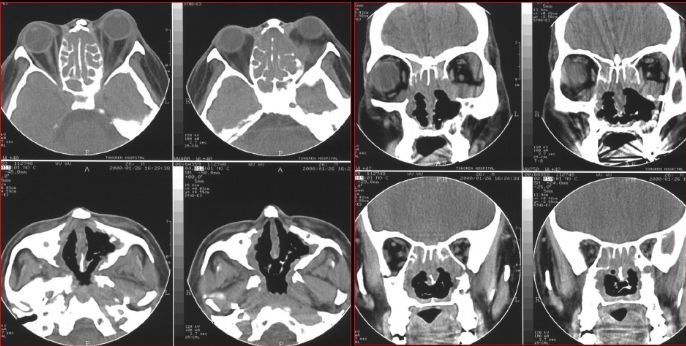

鼻窦炎—骨质改变

鼻窦炎—骨质增生

鼻窦炎—骨质增生及脑膜炎